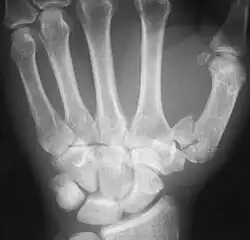

The first metacarpal bone or the metacarpal bone of the thumb is the first bone proximal to the thumb. It is connected to the trapezium of the carpus at the first carpometacarpal joint and to the proximal thumb phalanx at the first metacarpophalangeal joint.

The first metacarpal bone is short and thick with a shaft thicker and broader than those of the other metacarpal bones. Its narrow shaft connects its widened base and rounded head; the former consisting of a thick cortical bone surrounding the open medullary canal; the latter two consisting of cancellous bone surrounded by a thin cortical shell. [1]

The head is less rounded and less spherical than those of the other metacarpals, making it better suited for a hinge-like articulation.

The distal articular surface is quadrilateral, wide, and flat; thicker and broader transversely and extends much further palmarly than dorsally. On the palmar aspect of the articular surface there is a pair of eminences or tubercles which articulate with the radial and ulnar sesamoid bones of the thumb metacarpophalangeal joint; the lateral eminence is larger than the medial.

Fractures

Fractures to metacarpal bones account for 30-40% of all hand fractures, of which 25% occur in the first metacarpal (second to fractures to the fifth metacarpal bone). 80% of fractures to the first metacarpal occur at its base. [6]

Common fractures to the thumb metacarpal include Bennett's fracture and Rolando's fracture